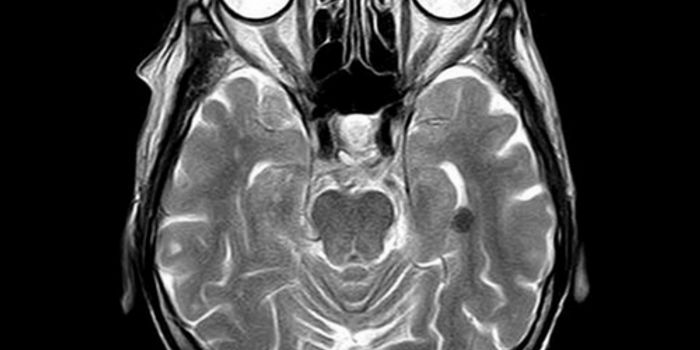

Cardiology is an ever-evolving branch of medicine concerned with disease and disorders of the heart. Cardiology trending provides articles and resources to keep you informed on risk factors, causes and prevention of heart disease, evidence-based research and advances in treatment.